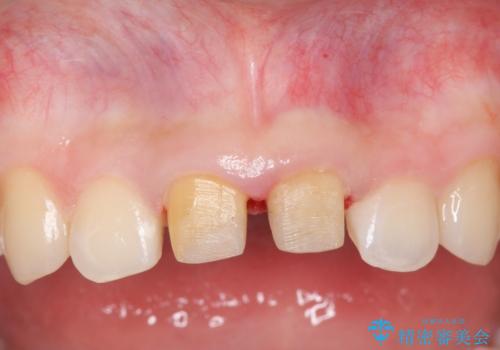

上の前歯は、小さいころにぶつけて折ったとのことで、神経が死んでおり、根の治療が必要な状態でした。

左上の前歯は神経が死んでおり治療が必要な状態でした。また、右上の前歯も根の先に感染がありましたので治療を行いました。

また、プラスチックでつぎはぎになっていたため、虫歯を取りしっかりとしたクラウン(被せもの)としました。